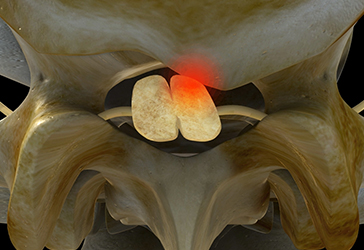

- 협착증, 퇴행성디스크 등 중증 척추 질환 치료 기간 - 2개월 이상

- 일상 생활에 지장이 없을 정도의 통증 감소를 목표로 2~3주 입원집중치료 또는 주2회 이상 집중치료를 한 뒤에 더 이상의 퇴행이 진행되지 않도록 지속적인 관찰 치료가 필요합니다.

단, 오랜 시간 동안 진행되어온 퇴행성 척추질환(퇴행성디스크, 척추관협착증), 뼈의 구조적인 이상 (척추분리증, 척추전방전위증,

척추이분증) 등은 병의 진행 상태에 따라 치료 기간이 달라질 수 있습니다.